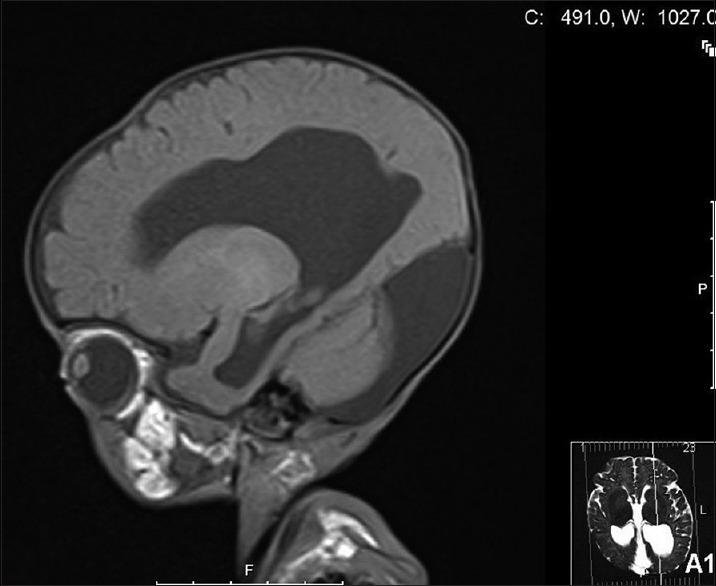

Dandy-Walker syndrome (DWS) is a rare brain malformation involving the cerebellum, and the fluid filled spaces around it, usually detected during the antenatal period or the early infancy. Clinically, it is characterized by mental retardation, developmental delay as well as cerebellar ataxia. It has been frequently associated with other conditions such as congenital heart diseases, primary hypothyroidism, and other disorders of the central nervous, gastrointestinal, genitourinary, and orthopedic systems. In this report, we describe a 3-month-old Saudi boy with the rare association of DWS with central diabetes insipidus, congenital central hypothyroidism, and type-2 renal tubular acidosis.

丹迪-沃克综合征(DWS)是一种罕见的涉及小脑及其周围充满液体空间的脑部畸形,通常在产前或婴儿早期被发现。临床上,其特征为智力迟钝、发育迟缓以及小脑共济失调。它常与其他病症相关,如先天性心脏病、原发性甲状腺功能减退以及中枢神经、胃肠、泌尿生殖和骨科系统的其他疾病。在本报告中,我们描述了一名3个月大的沙特男孩,其患有丹迪-沃克综合征并罕见地合并中枢性尿崩症、先天性中枢性甲状腺功能减退和2型肾小管酸中毒。